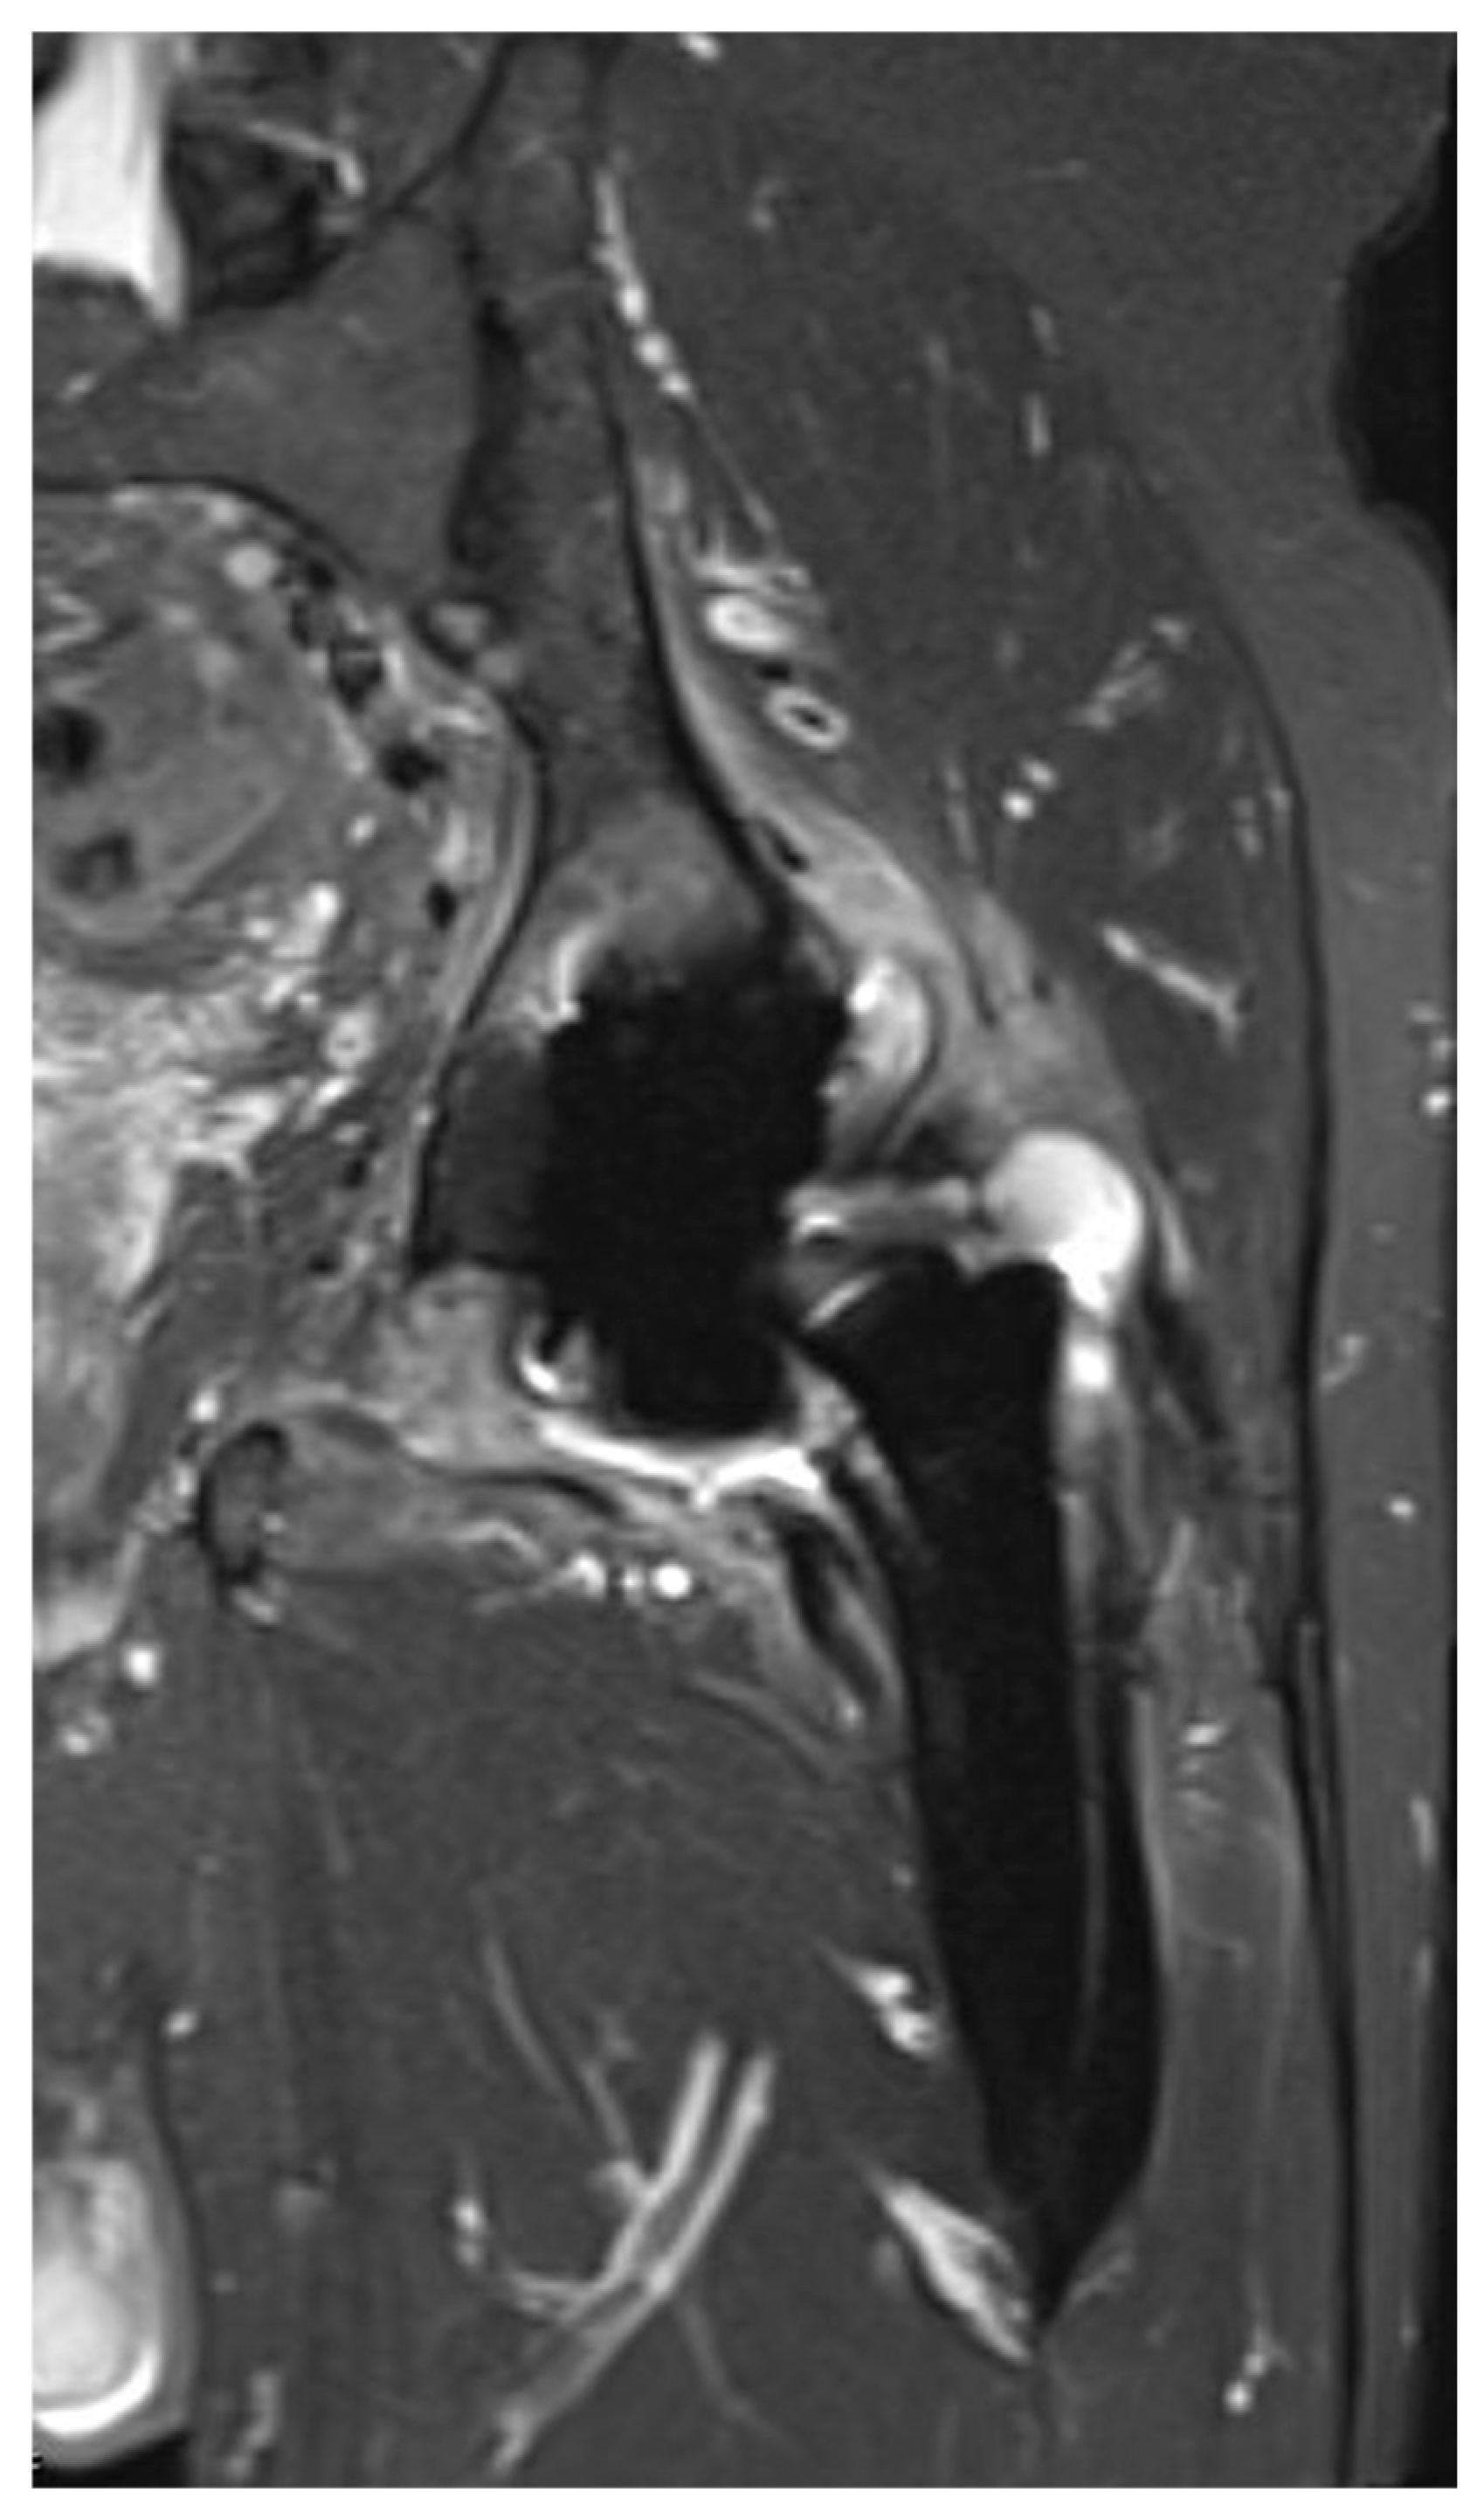

3.3. Imaging Findings

| Parameter | Cohort (n = 46) |

|---|---|

| Any pathological finding, n (%) | 45 (97.8) |

| Location | |

| Anterolateral musculature | 6 (13.0) |

| Greater trochanter | 11 (23.9) |

| Iliotibial band | 2 (4.3) |

| Gluteal muscles | 4 (8.7) |

| Iliopsoas muscle | 8 (17.4) |

| Obturator muscles | 4 (8.7) |

| Sacroiliac joint | 1 (2.2) |

| Soft tissue and musculature adjacent to hip joint | 7 (15.2) |

| Joint effusion, n (%) | 34 (73.9) |

| Amount | |

| Small | 4 (8.7) |

| Moderate | 22 (47.8) |

| Large | 8 (17.4) |

| Location extension | 30 (65.2) |

| Greater trochanter | 8 (17.4) |

| Iliopsoas muscle | 7 (15.2) |

| Surrounding soft tissue and musculature | 5 (10.8) |

| No joint effusion, n (%) | 12 (26.1) |

| Pathological finding | |

| Sinus tract | 5 (10.8) |

| Osteomyelitis | 1 (2.2) |

| Edematous changes | |

| Greater trochanter | 3 (6.5) |

| Iliopsoas | 1 (2.2) |

| Soft tissue and musculature adjacent to hip joint | 2 (4.3) |

| Capsule thickening, n (%) | 11 (23.9) |